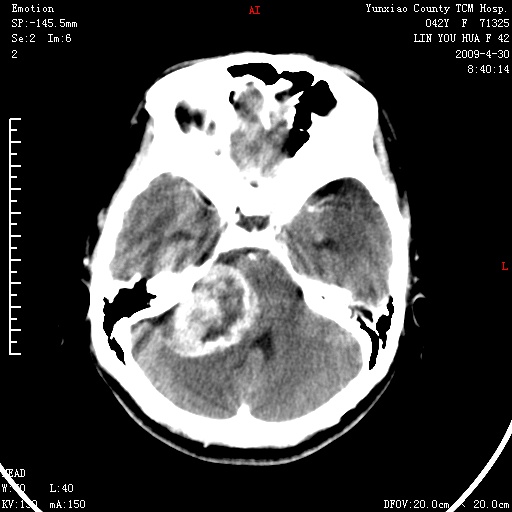

右侧桥小脑角区肿瘤,高密度囊变有显著强化,骨窗见内听道显著扩大,考虑听神经瘤可能性大

1)右侧听神经瘤。2)阻塞性脑积水。

内听道扩大,支持考虑听神经瘤可能性大。